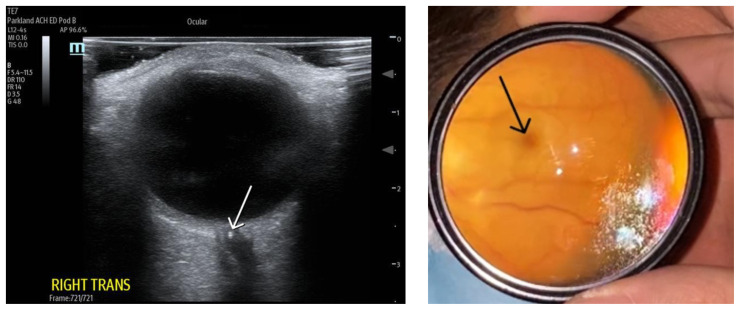

Central retinal artery occlusion (CRAO) is a rare emergency department presentation with high morbidity and potential for long-term vision loss. Additionally, this finding requires an expeditious embolic workup for possible systemic pathology (i.e., stroke). The gold standard for diagnosis is visualization of a pale retina with a "cherry-red spot" on the fovea seen under dilated fundoscopic examination. However, performing a dilated fundoscopic exam is often not practical and technically challenging in the emergency room setting. Alternatively, point of care ultrasound is an inexpensive, non-invasive tool that is already highly utilized in the emergency department and can aid in diagnosis. In the case described in this report, a 66-year-old female presented to the emergency department with painless, monocular vision loss. Ultrasound showed a hyperechoic density on the distal aspect of the optic nerve ("retrobulbar spot sign") and dilated fundoscopic exam showed right eye pale macula with cherry red spot, all consistent with CRAO. Here we present a case that suggests an opportunity for improvement in evaluation of monocular vision loss in the emergency department by adding bedside ocular ultrasound to aid in more rapid diagnosis of CRAO.